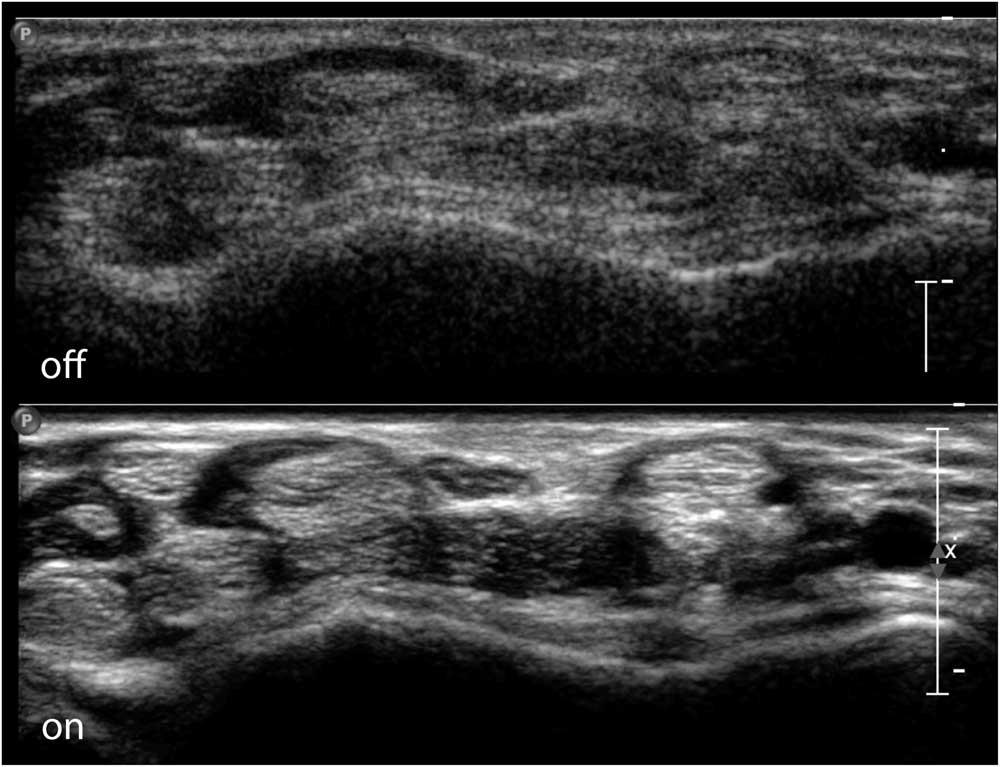

Many factors influence how a muscle or nerve will look on the screen. Every ultrasound machine has a specific set of image-forming properties that determine how the software handles the incoming sound waves from the transducer elements. These system settings, such as the overall gain (i.e., the volume knob), image depth, focal zones, image compression, the use of harmonic waves and spatial or time-averaging techniques create a specific “look” (Figure 3), and most users will become familiar over time with their standard preset images of muscle or nerve. If image clarity and resolution are paramount, as in nerve ultrasound, one wants a machine that can utilize all image optimization tools to provide the best picture. However, if obtaining reproducible and quantifiable images of muscle echogenicity is the goal, a machine with precisely defined preset and no image-enhancing features is ideal (Figure 4).

Figure 4 Transverse image of the ventral wrist crease, showing the flexor tendons of the wrist and fingers and the median nerve in the middle on top. The top half of the image shows a raw image format without additional image enhancing; the bottom half shows full use of image-enhancing features with clear delineation of the nerve and tendon contours. Images captured on a Philips IU22 system with a linear 5-17 MHz probe and MSK preset (Philips Healthcare, Eindhoven, The Netherlands).